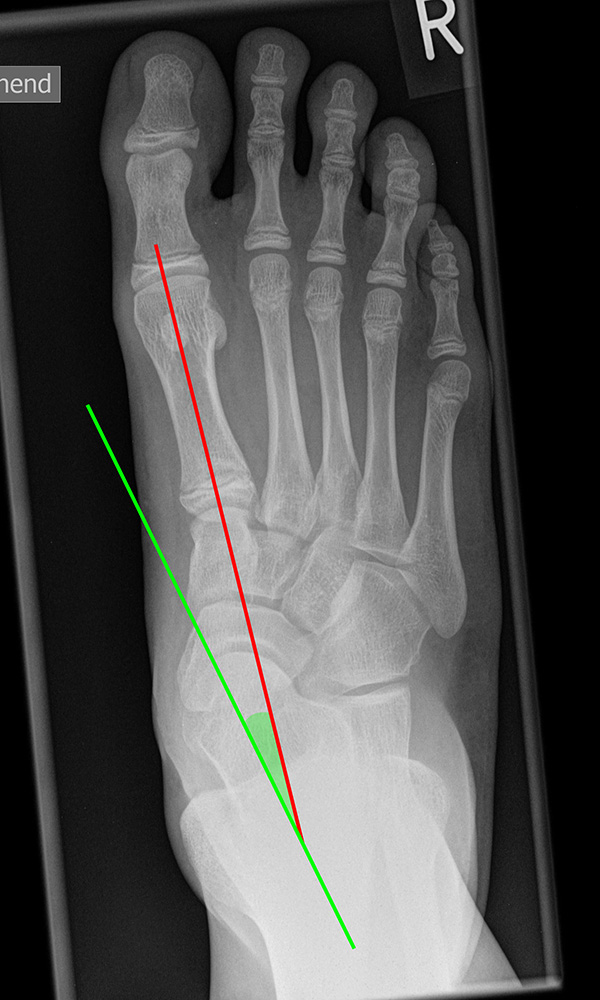

DMAA (Distal metatarsal artikular angle, Syn. Gelenkflächenwinkel): Winkel zwischen der Achse des Os metatarsale I (rot) und dem Lot auf die distale Gelenkflächenebene (blau) des Os metatarsale I. Die Gelenkflächenebene (grün) wird definiert durch zwei Punkte, welche die mediale und laterale Begrenzung der Gelenkfläche definieren (Norm: <10° 5). Die Projektion des DMAA ist stark abhängig von der Rotation des Os metatarsale I 7. Daher ist bei der operativen Behandlung des Hallux valgus eine Beurteilung häufig erst nach Korrektur der Pronationsstellung des Os metatarsale I möglich. Tendenziell wird der DMAA auf präoperativen Röntgenaufnahmen überschätzt.

Beurteilung eines Metatarsus adductus

Medial wird eine Linie von der medialen Begrenzung des TMT1-Gelenks und der medialen Begrenzung des Talonavikulargelenks (TN) gezeichnet. Auf der lateralen Seite des Fußes wird eine zweite Linie von der lateralen Begrenzung des Calcaneocuboid-Gelenks (CC) zur lateralen Begrenzung des TMT5-Gelenks gezeichnet. Die Mittelpunkte beiden Linien werden verbunden (blau). Der Winkel zwischen der Achse des Os metatarsale II (rot) und dem Lot auf Verbindungslinie (grün) ist ein Maß für die Stellung des Vorfußes zur Fußwurzel. Dieser Wert dient zur Charakterisierung eines Pes adductus. Ein Pes adductus kann zu einem normwertigem Intermetatarsale I/II Winkel führen, obwohl klinisch eine ausgeprägte Hallux valgus Deformität vorliegt 8. (Norm: ±13° 9.